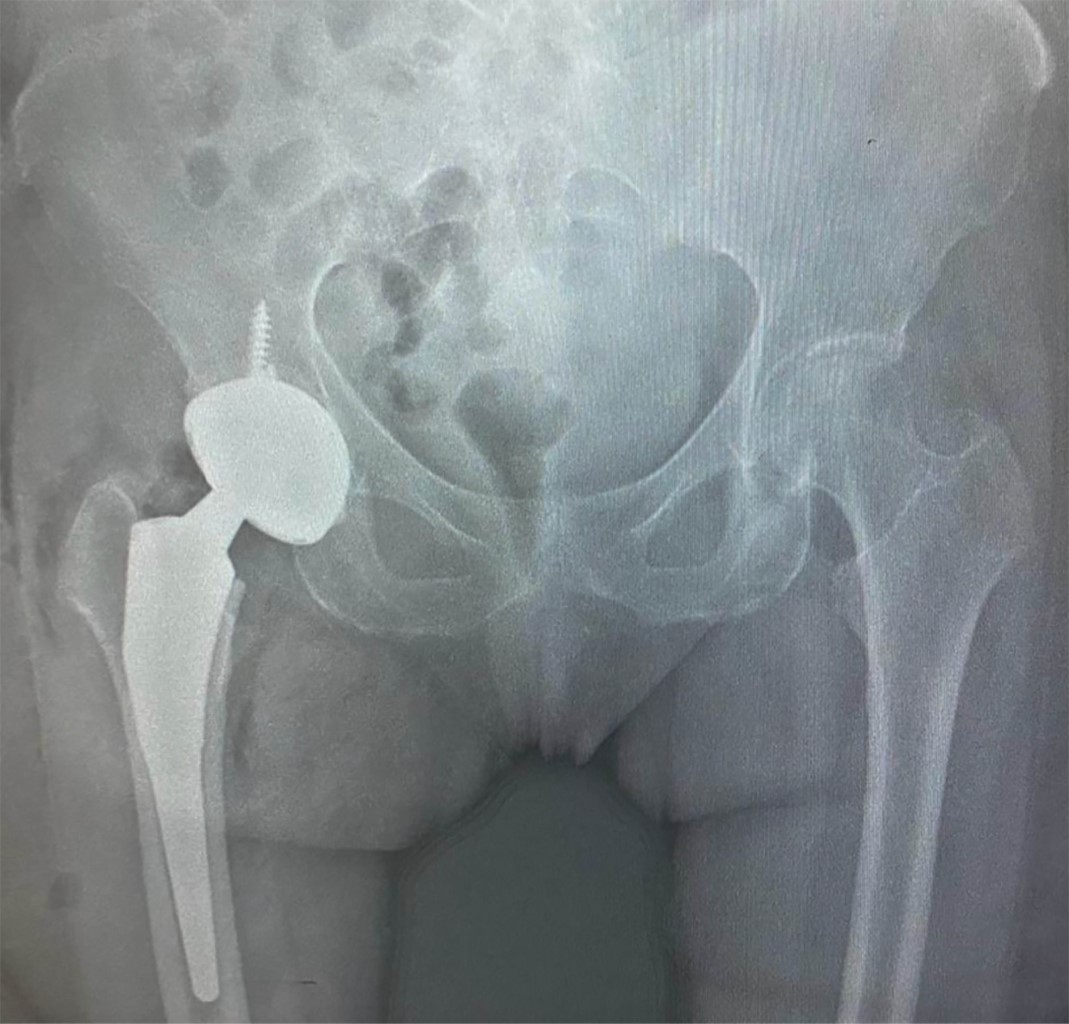

Radiológicamente presenta pérdida del espacio articular en cadera derecha, abundantes osteofitos, esclerosis en acetábulo.

En quirófano, con el paciente bajo bloqueo mixto, se realizó un reemplazo total de cadera derecha mediante un abordaje posterior, con prótesis de doble movilidad G7 (por antecedente de espondiloartropatía con anquilosis lumbar), con vástago Taper lock (Zimmer Biomet). Durante el procedimiento se observó de manera macroscópica la presencia de zonas oscuras en cabeza y cuello femoral, propias de depósitos AHG (Figura 2). El procedimiento finalizó sin complicaciones, con control radiológico postquirúrgico (Figura 3). El examen patológico macroscópico refirió cabeza femoral con manchas obscuras con parches en tejido óseo y cartilaginoso; la imagen histopatológica se muestra en la Figura 4.

Figura 1

Figura 3